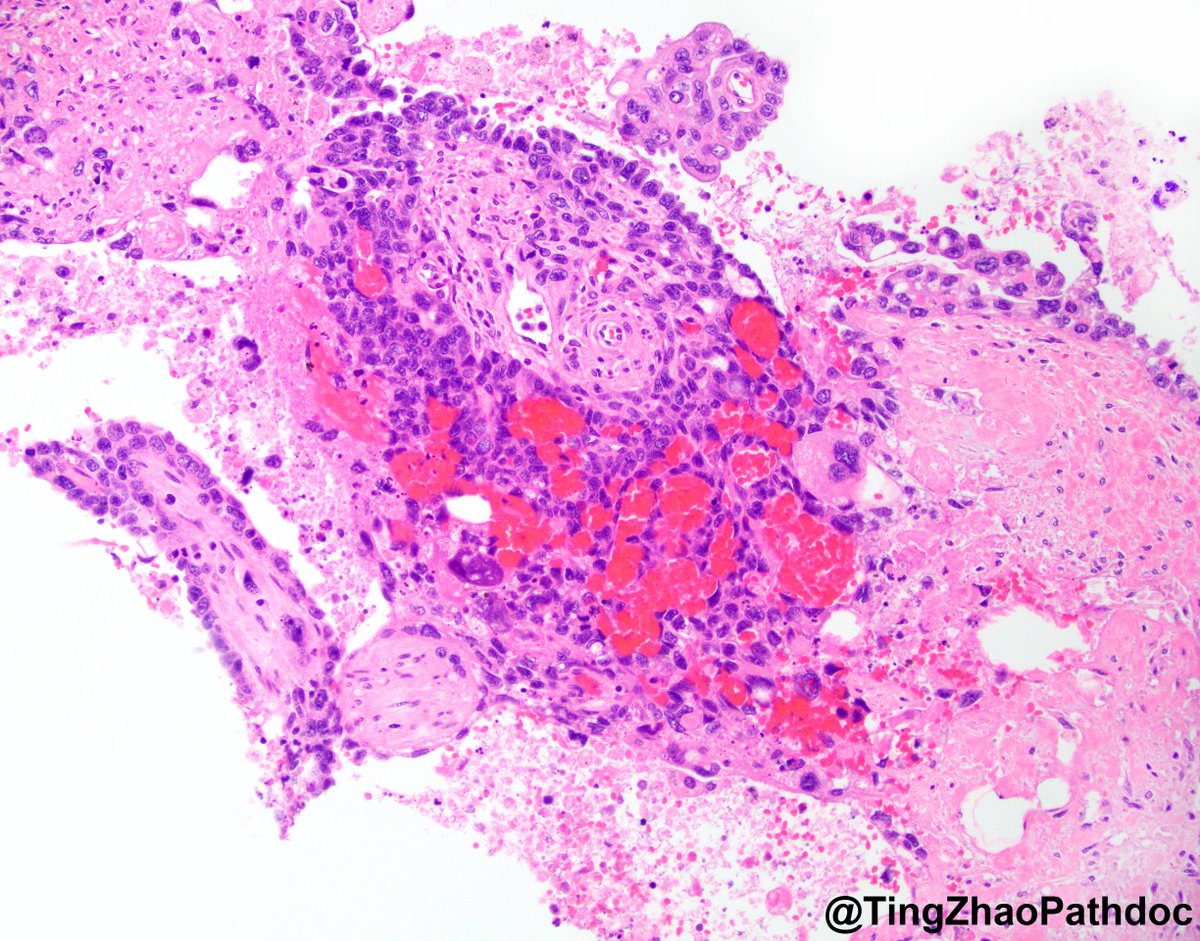

@TingZhaoPathdoc

Ting Zhao, MD

17 days

80s M, cystectomy. What is your diagnosis? #PathTwitter @MGBpathology @MGHPathology

23 days

@MGBpathology @MGHPathology Metastatic prostatic adenocarcinoma to testis #GUpath https://t.co/G9UDkqHNsw